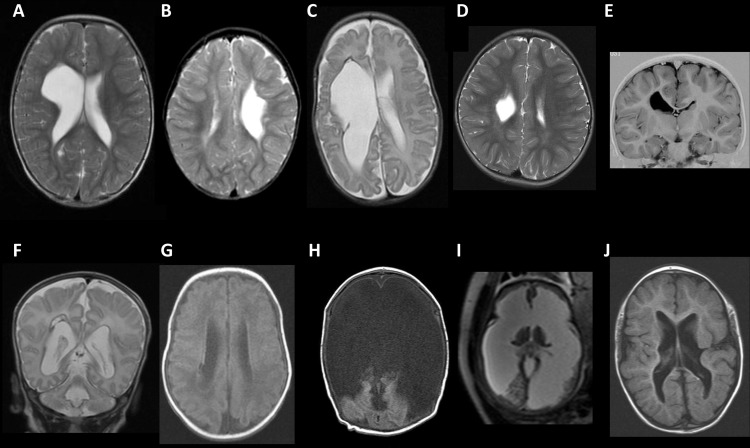

Porencephaly is a rare neurological disorder characterized by cysts or cavities within the brain’s cerebral hemispheres. These fluid-filled spaces can affect brain function depending on their size and location. Porencephaly can be congenital (present at birth) or acquired after brain injury.

- Imaging studies: MRI and CT scans reveal cystic cavities in the brain